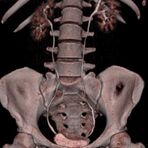

Wirbelsäule

• Darstellung von Frakturen, Tumoren und Bandscheibenveränderungen

Extremitäten

• bei komplizierten Frakturen z. B. in der Nähe von Gelenken oder im Bereich der Handwurzel und Fußwurzel